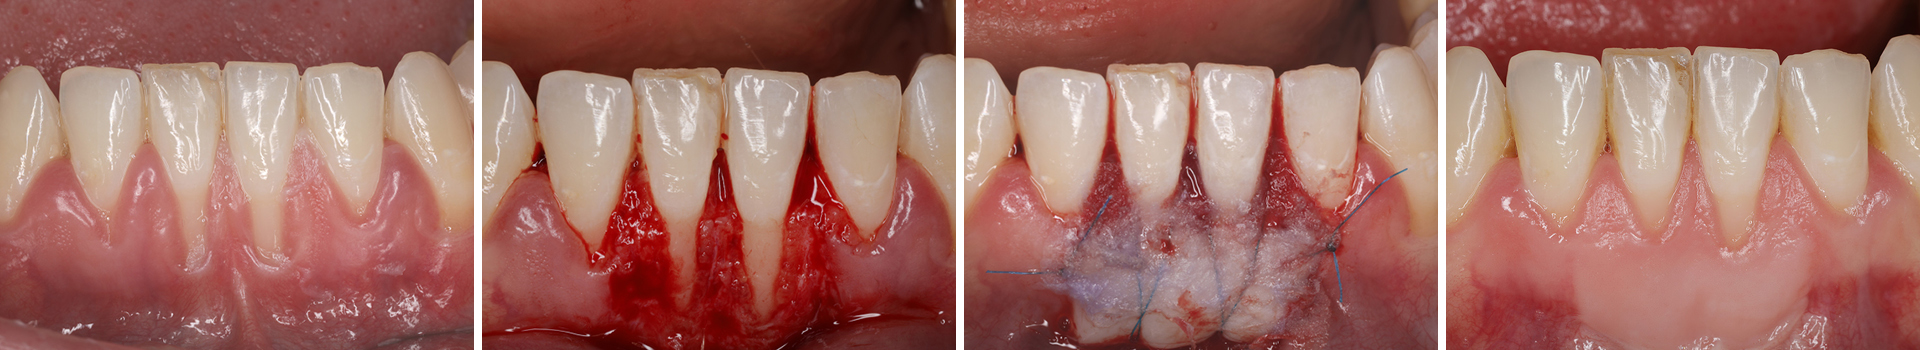

Abbildung 1

Klinische Ausgangssituation mit Rezessionen vom Typ 1 in regio 31/41 und unzureichender Breite und Dicke an keratinisiertem Gewebe.